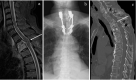

Figure 3.

Postadmission images of the thoracic spine. (a) Sagittal magnetic resonance imaging scan after the appearance of paralysis showing progressed epidural abscess and spinal cord compression at the level of T1-2. (b) Anteroposterior thoracic spine view of the postoperative radiograph showing spinal instrumentation applied at C7-T3 levels. (c) Sagittal computed tomography scan 6 months postoperatively showing solid bony fusion of T1-2.